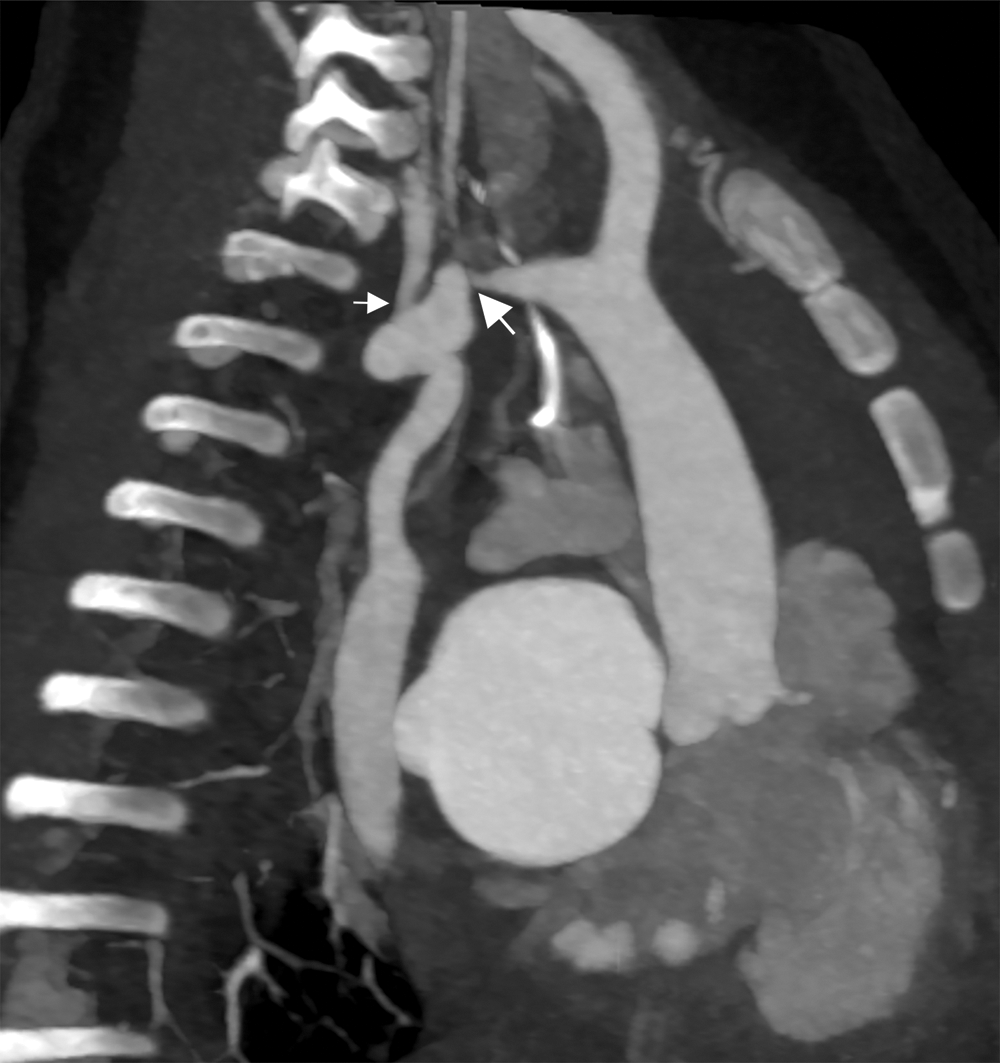

Cardiac CT (Figs. 2–4) identified an ascending aorta that gave rise to dilated common carotid arteries and an extremely tortuous and stenotic right aortic arch. The right subclavian artery originated beyond the area of severe arch stenosis with an additional area of narrowing at its origin. Collateral vessels were seen in the right side of the neck. A long and relatively narrow right-sided dorsal aortic root passed in a caudal direction where it was joined by an equally long but larger left-sided dorsal aortic root reflecting ductal flow in utero. The dorsal roots fused below the level of the carina. The descending aorta was also right-sided but crossed to the left at the level of the diaphragm. The left-sided dorsal root remnant supplied an aberrant left subclavian artery, a dilated left vertebral artery, and collateral vessels in the left side of the neck. There was no evidence of a double aortic arch.

Figure 2: Cardiac CT—Sagittal oblique maximum intensity projection multiplanar reconstruction (MIP/MPR) on admission. Extremely tortuous and stenotic right aortic arch. Severe discrete coarctation (large arrow). The right subclavian artery originates beyond the area of severe arch stenosis with an additional area of narrowing at its origin (small arrow)